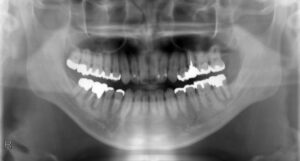

下顎小臼歯2本欠損症例(先天性欠損)

BEFORE AFTER 39歳男性/下2本欠損/インプラント埋込手術 【治療内容】 下顎第二小臼歯が左右とも先天性の欠…